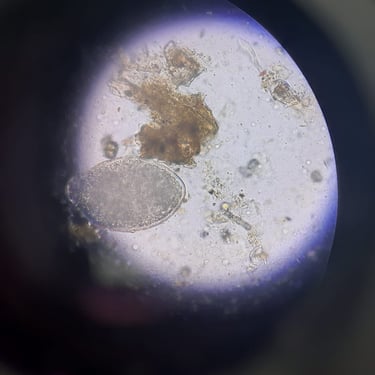

Análisis coprológico: Para la evaluación de parásitos internos, como lombrices intestinales u otros organismos presentes en las heces.

Citología: Examen microscópico de muestras celulares para identificar células anormales, lo cual es útil en la detección de infecciones y otros trastornos.